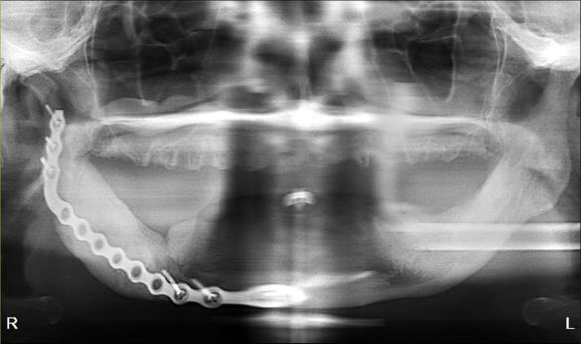

Case 2

The patient is a 54-year-old female with a history of Stage 4 metastatic breast cancer treated with chemotherapy and radiation. She was treated with zoledronic acid (Zometa) beginning in June 2020. The patient was referred to Denver Health OMS by her dentist regarding non-healing extraction sites and additional extractions. In mid-2022, about three months prior to the referral, her dentist had extracted teeth #29 to #31. On examination, the patient had Stage 2 MRONJ along with painful, periodontally compromised, non-restorable teeth. Following a consultation with oncology and infectious disease, the decision was made to debride the MRONJ area and remove the remaining teeth in the operating room with the patient on long-term antibiotic coverage. Within two to three months, MRONJ had recurred and in April 2023, the patient subsequently underwent a right posterior mandibular resection with an antibiotic spacer placed in the resected area.